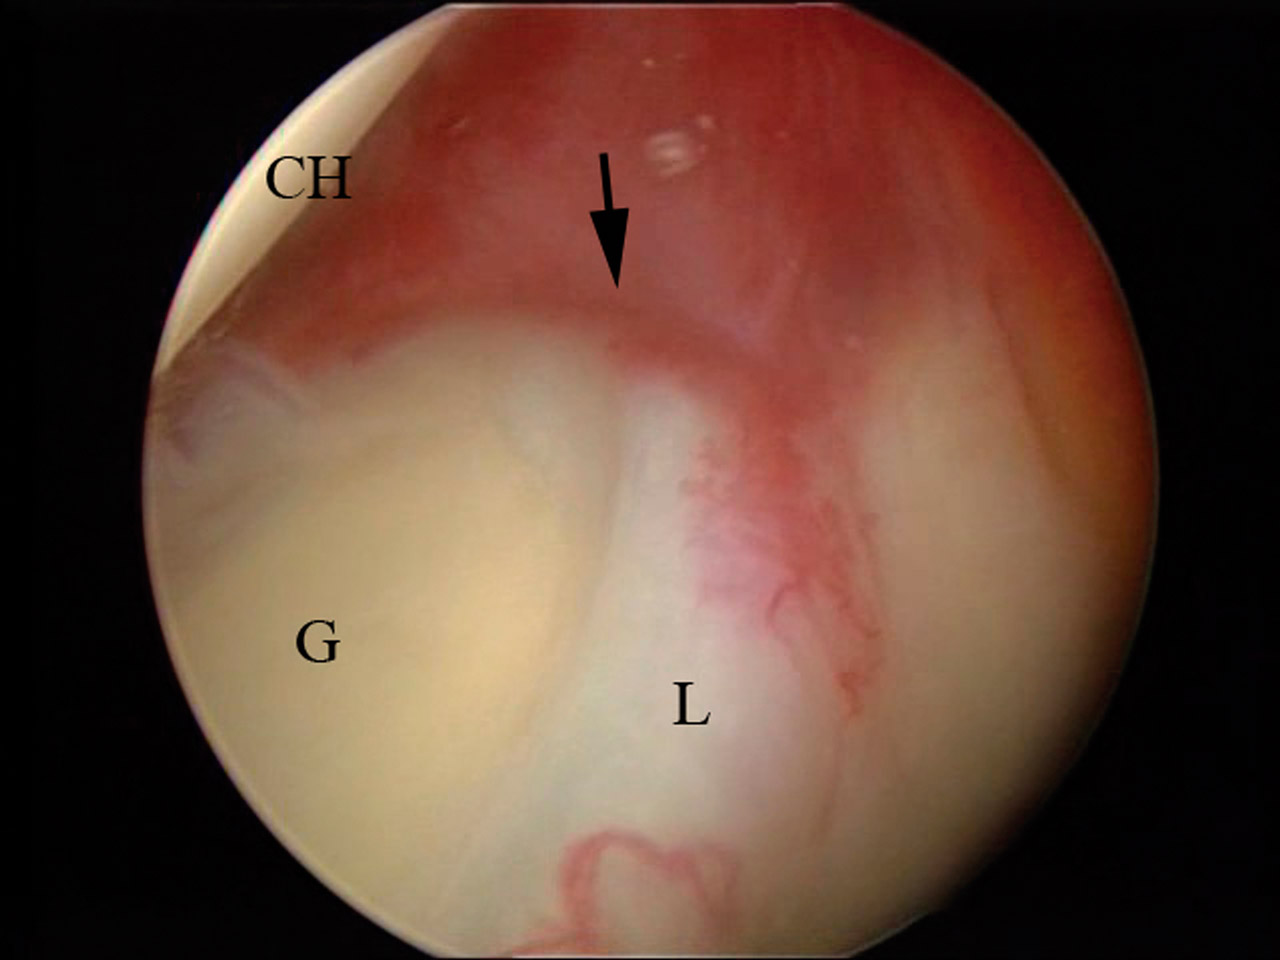

Dada la mala respuesta al tratamiento médico, se decidió realizar una descompresión subacromial artroscópica. En la exploración intraarticular se objetivó la ausencia del TPLB (Figura 1) con un labrum sin muestra de rotura actual o antigua. Se realizó una bursectomía artroscópica con vaporizador y acromioplastia con motor artroscópico. El postoperatorio trascurrió sin incidencias, presentando una recuperación clínica y funcional completa. Ante el hallazgo casual de la agenesia del músculo bíceps braquial, se revisaron las imágenes preoperatorias de RM, confirmándose la ausencia del tendón en la corredera bicipital, la cual se observó hipoplásica (Figura 2). Se realizó un estudio ecográfico contralateral donde también se objetivó que la agenesia bicipital era bilateral y una corredera hipoplásica (Figura 2).

Es necesario encontrar herramientas clínicas y pruebas imagen que nos ayuden en el diagnóstico diferencial entre lesión o agenesia del TPLB. Los test de O’Brien y Speed no son buenos para diagnosticar lesión aislada del tendón bicipital y suelen ser positivos cuando se añaden alteraciones del manguito. La ausencia del signo de Popeye y la falta de dolor a la palpación de la corredera bicipital son signos constantes en todos los estudios(1)(2). En la ecografía y la RM, los signos claves son falta de retracción del vientre muscular del bíceps, hipoplasia del surco bicipital(1)(2) e hipertrofia del ligamento semicircular del húmero(4). En nuestro caso, se trató de un hallazgo artroscópico casual, sin ser objetivado en la RM preoperatoria, que se confirmó posteriormente ante la del TPLB y una corredera bicipital hipoplásica. El estudio ecográfico del hombro contralateral confirmó que se trataba de una agenesia bilateral.